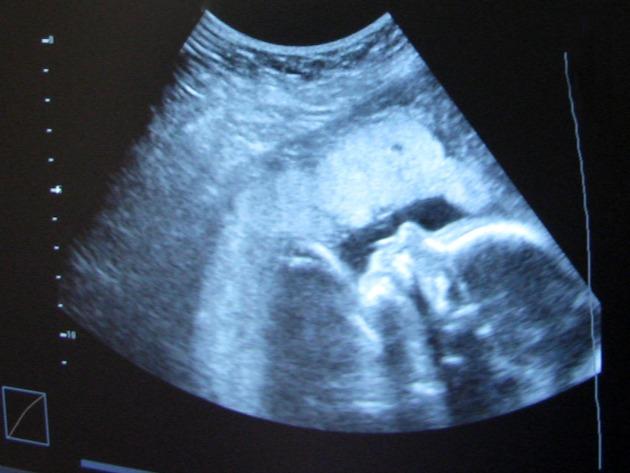

Prema široko rasprostranjenoj definiciji “pilula za dan poslije” ili “pilula za jutro poslije” (morning after pill) tableta je namijenjena za hitnu kontracepciju, koja se koristi nakon nezaštićenog spolnog odnosa kako bi se spriječila neželjena trudnoća. Ovakvom definicijom već se u samom startu manipulira s pojmom trudnoća koja bi trebala početi ne više trenutkom začeća nego tek kad se embrij implantira u maternicu, negdje oko 7. dana nakon začeća. Naime takva je definicija prvi put donesena 1972. od strane American College of Obstetricians and Gynecologists.

Prema tome, kako proizlazi iz ovog dosad rečenog, pilula za dan poslije prvenstveno djeluje na način da sprječava razvoj embrija, onemogućujući mu nidaciju (ugnježđenje) u maternicu. Ne radi se dakle o kontraceptivnom nego prije anti-nidacijskom učinku. Znanstvena očitost takvog anti-nidacijskog učinka opovrgava, prema tome, i samu terminologiju koja se koristi za ovaj proizvod: ne radi se o kontraceptivnom mehanizmu (budući da se, kako smo vidjeli, sprječavanje začeća događa u malom postotku slučajeva), već o izrazito abortivnom mehanizmu koji se manifestira nakon što je došlo do začeća, kad je već započeo razvoj novog ljudskog života.

„Pilula za dan poslije je preparat na hormonskoj bazi i koja, uzeta unutar 72 sata nakon spolnog odnosa, za kojeg se pretpostavlja da bi mogao biti plodan, razvija pretežno “antinidacijski” mehanizam, tj. sprječava da se eventualno oplođeno jajašce (a to je ljudski embrij), sad već razvijeno do stadija blastociste, smjesti na stijenku maternice, pomoću mehanizma koji mijenja samu stijenku. Konačni će, dakle, rezultat biti izbacivanje i propadanje tog embrija. Jedino u slučaju da je takva pilula uzeta nekoliko dana prije ovulacije, ponekad bi mogla djelovati s mehanizmom koji blokira ovulaciju (u tom bi se slučaju radilo o tipičnoj “kontracepciji”).

[…] Jasno je da dokazano “antinidacijsko”djelovanje pilule za dan poslije, u stvarnosti, nije ništa drugo nego pobačaj ostvaren kemijskim sredstvima. Niti je intelektualno dosljedno niti znanstveno opravdano tvrditi da se ne radi o istoj stvari. Uostalom, čini se poprilično jasnim kako je namjera onih koji traže ili nude pilulu izravno usmjerena na prekid eventualno započete trudnoće, točno kao u slučaju pobačaja. Trudnoća, naime, počinje začećem a ne implantacijom embrija na stijenku maternice, kako se naprotiv pokušava implicitno sugerirati. Iz toga proizlazi da se, s etičkog gledišta, ista apsolutna nedopuštenost koja se odnosi na abortivne prakse, odnosi i na širenje, propisivanje i korištenje pilule za dan poslije“.